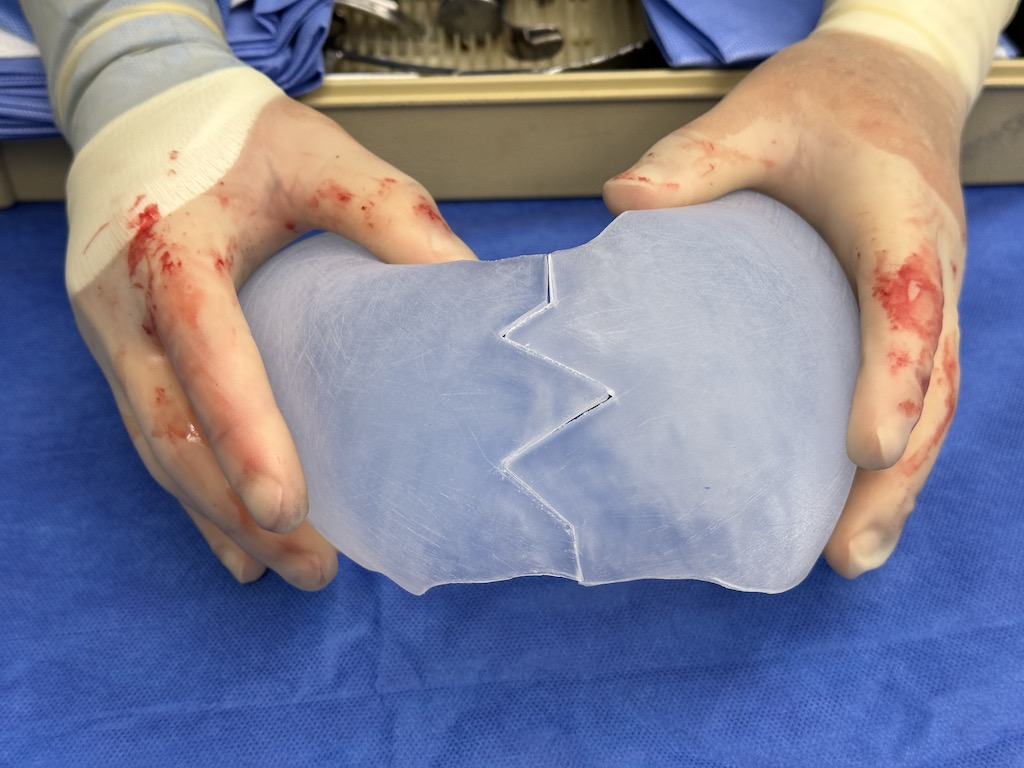

Desire for major head reshaping with a taler and wider head shape.

Placement of large two piece custom skull implant through a sagittal scalp incision.

Desire for major head reshaping with a taler and wider head shape.

Placement of large two piece custom skull implant through a sagittal scalp incision.